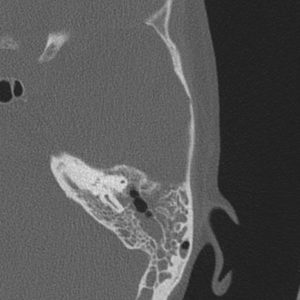

Viêm tai xương chũm

Lượt xem: 2014» 27-01-2019 -